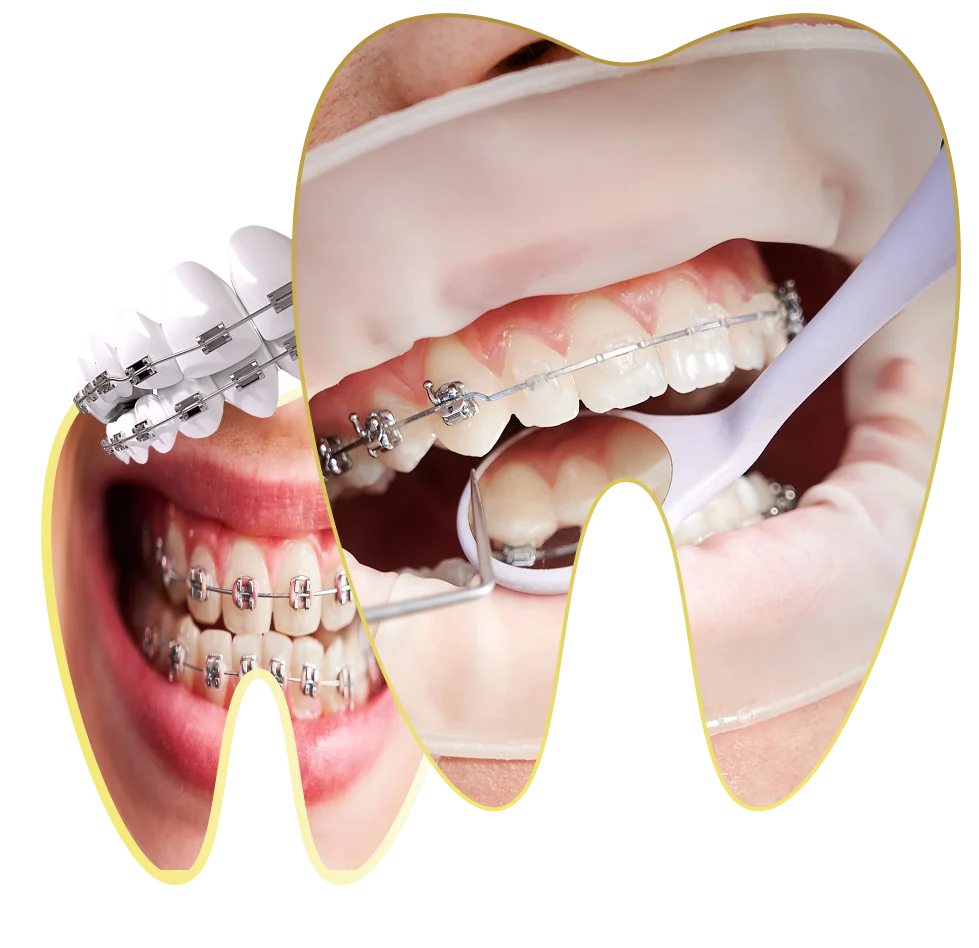

د. حنان ابو الحسن ، مؤسسة Lavender Aesthetic Clinics، هي طبيبة أسنان متخصصة في تركيبات الاسنان ,زراعة الاسنان , حشو عصب ,حشو تجميلي